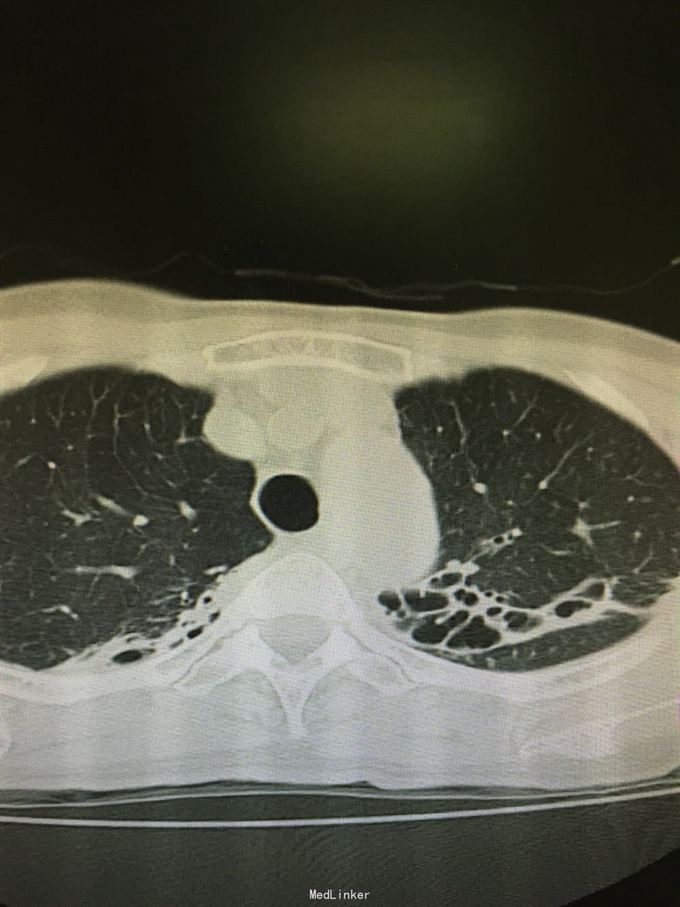

63岁女性,因“反复咳嗽、咳痰5年,加重1年”入院。

查体:双肺呼吸音粗,双上肺可闻及哮鸣音,双下肺可闻及干湿性罗音。外院胸片示两上中肺可见片装阴影,密度不均匀,边缘模糊,左中肺病灶中可见一椭圆形透光区,大小1.5*2.0cm;双肺纹理增粗、紊乱。考虑继发性肺结核(III上/上中。进展)我院胸片考虑支气管扩张。

诊断:支气管扩张并感染;肺结核?。入院后予甲磺酸左氧氟沙星200mlQd静滴治疗。

肺结核患者易并发支气管扩张。该患者影像学表现为碎饼干渣样,为较典型结核播散灶。支气管扩张表现也较典型。